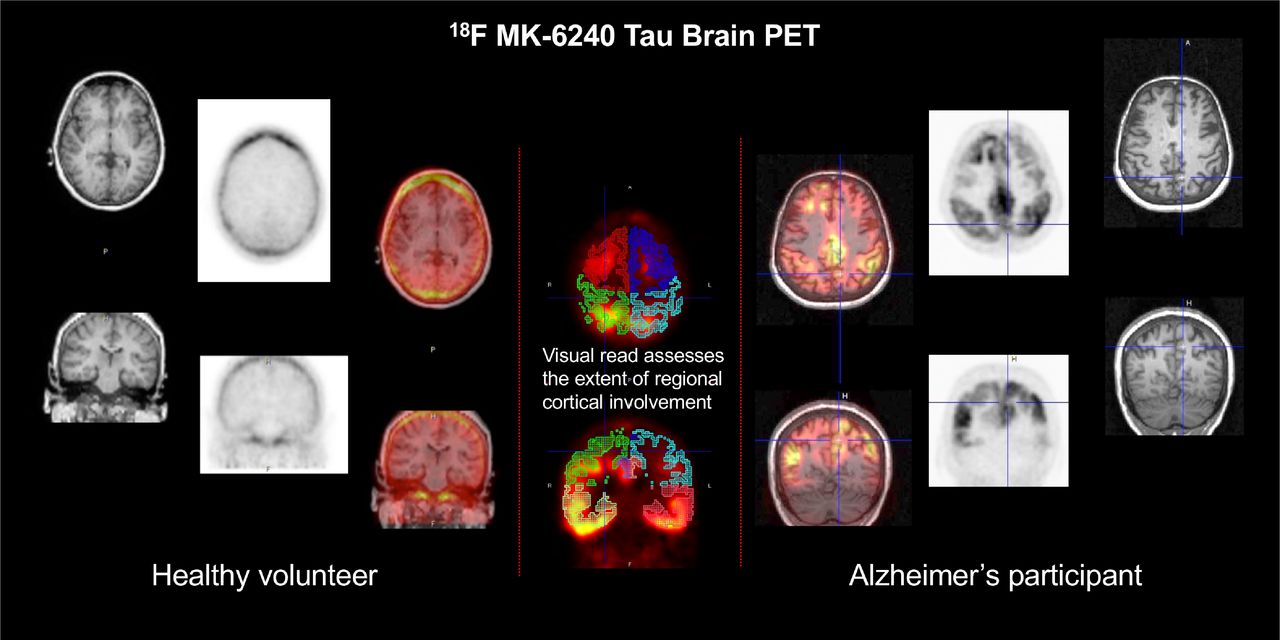

Zebra Medical Vision Announces FDA 510(k) Clearance of, A Visual Interpretation Algorithm for Assessing Brain,

A Visual Interpretation Algorithm for Assessing Brain, Preclinical evaluation and preliminary clinical study of